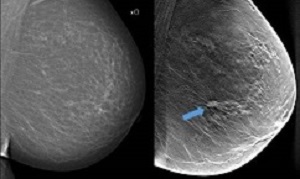

In traditional mammography screening, all breast tissue is captured in a single image. Breast tomosynthesis, on the other hand, is three-dimensional and works according to the same principle as what is known as tomography. This means that several low-dose x-ray images are taken of the breast from different angles, which are reconstructed by a computer to show thin layers of the breast. With more and improved image information and less overlapping tissue structures, the chance of detecting tumours increases.

Background: Digital breast tomosynthesis is an advancement of the mammographic technique, with the potential to increase detection of lesions during breast cancer screening. The main aim of the Malmö Breast Tomosynthesis Screening Trial (MBTST) was to investigate the accuracy of one-view digital breast tomosynthesis in population screening compared with standard two-view digital mammography.

Interpretation: Breast cancer screening by use of one-view digital breast tomosynthesis with a reduced compression force has higher sensitivity at a slightly lower specificity for breast cancer detection compared with two-view digital mammography and has the potential to reduce the radiation dose and screen-reading burden required by two-view digital breast tomosynthesis with two-view digital mammography.